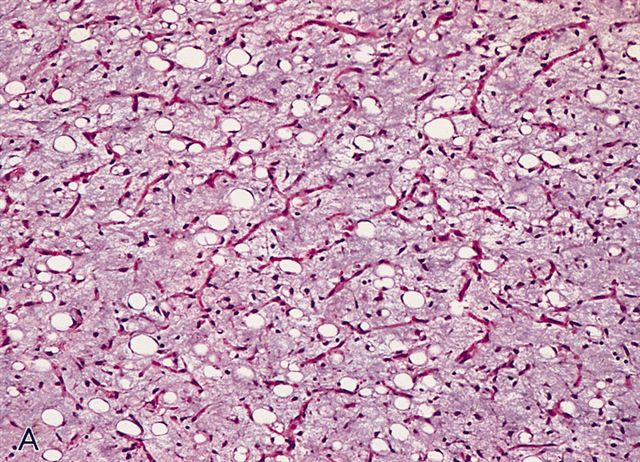

- Low grade

- Paucicellular with monomorphic, stellate or fusiform shaped cells without atypia; striking in their blandness, so much so that any significant pleomorphism should cause one to pause

- Prominent plexiform vasculature (delicate thin walled arborizing and curving capillaries that form a network reminiscent of chicken wire fencing)

- These are striking because of the overall background paucicellularity and are still present in high grade tumors but are much less obvious

- Numerous signet ring lipoblasts, particularly at periphery of lobules

- Mucoid matrix is rich in hyaluronic acid that may form large mucoid pools (so called pulmonary edema pattern)

- Will be positive for stromal mucin stains such as Alcian blue (see Microscopic (histologic) images)

- Typically there is no significant mitotic activity

- Can contain large areas of mature adipocytic differentiation